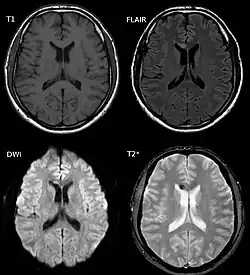

A lesão axonal difusa é difícil de ser detectada, já que não aparece bem em tomografias computadorizadas ou outras técnicas de imagem macroscópicas, embora apareça microscopicamente.[9] No entanto, existem características típicas da LAD que podem ou não aparecer em TCs. A lesão difusa tem mais lesões microscópicas do que lesões macroscópicas e é difícil de detectar com TC e Ressonância Magnética, mas pode haver suspeita quando pequenos sangramentos são visíveis no corpo caloso ou no córtex cerebral.[34] A RM é mais útil do que a TC para detectar características de LAD nos períodos subagudo e crônico.[35] Estudos mais recentes, como em imagens do Tensor de Difusão, são capazes de demonstrar o grau de lesão do trato de fibras da substância branca, mesmo quando a ressonância magnética padrão é negativa. Como o dano axonal na LAD é em grande parte resultado de cascatas bioquímicas secundárias, ele tem um início tardio, podendo uma pessoa com LAD que inicialmente parece bem piorar mais tarde. Dessa forma, a lesão é com frequência mais grave do que se prevê inicialmente, e os médicos devem suspeitar de LAD em qualquer paciente cujas TCs pareçam normais, mas que apresentem sintomas como perda de consciência.[9]

Mesmo a ressonância magnética sendo mais sensível do que a tomografia computadorizada, ainda está sujeita a falsos negativos porque a LAD é identificada pela procura de sinais de edema, que nem sempre estão presentes.[33]